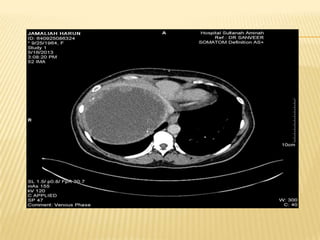

CT LIVER

IMAGING  Usg HBS Huge heterogenous cystic mass in the right liver lobe measuring > 20.5cm X 12cm.Presence of gallstone in GB.IHD and CBD not dilated Imp : suggestive of hydatid cyst with diffrential of amoebic liver abcess *** further history : h/o of multiple visits to egypt within past few years. Last visit was in feb 2013 whr she took local salad dish with grilled fish and snails delicacies